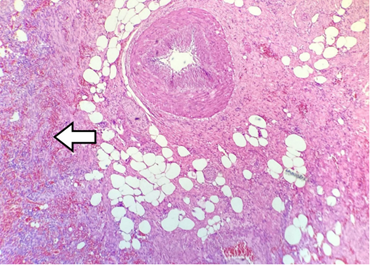

Se presenta el caso de un hombre de 84 años, con antecedentes de hipertensión arterial controlada y enfermedad pulmonar obstructiva crónica, quien consultó por dolor tipo cólico en el hemiabdomen superior, exacerbado por la ingesta de alimentos, irradiado al área periumbilical. Al examen físico había dolor en el hipocondrio derecho, masa palpable y signo de Murphy positivo. Los paraclínicos mostraron leucocitosis leve y transaminasas discretamente elevadas. La ecografía no identificó la vesícula biliar, por lo que se realizó una tomografía computarizada que mostró gas en la pared vesicular y el segmento V del hígado (Figura 1), sugiriendo colecistitis enfisematosa con posible ruptura. Durante la cirugía laparoscópica se identificó un plastrón inflamatorio, por lo que se optó por convertir a cirugía vía abierta; así se encontró una perforación en el tercio inferior de la vesícula y contenido fibrinopurulento (Figura 2). El paciente evolucionó favorablemente, recibiendo alta tras seis días. El análisis histopatológico confirmó inflamación severa, necrosis focal y hemorragia reciente en la pared vesicular (Figura 3).